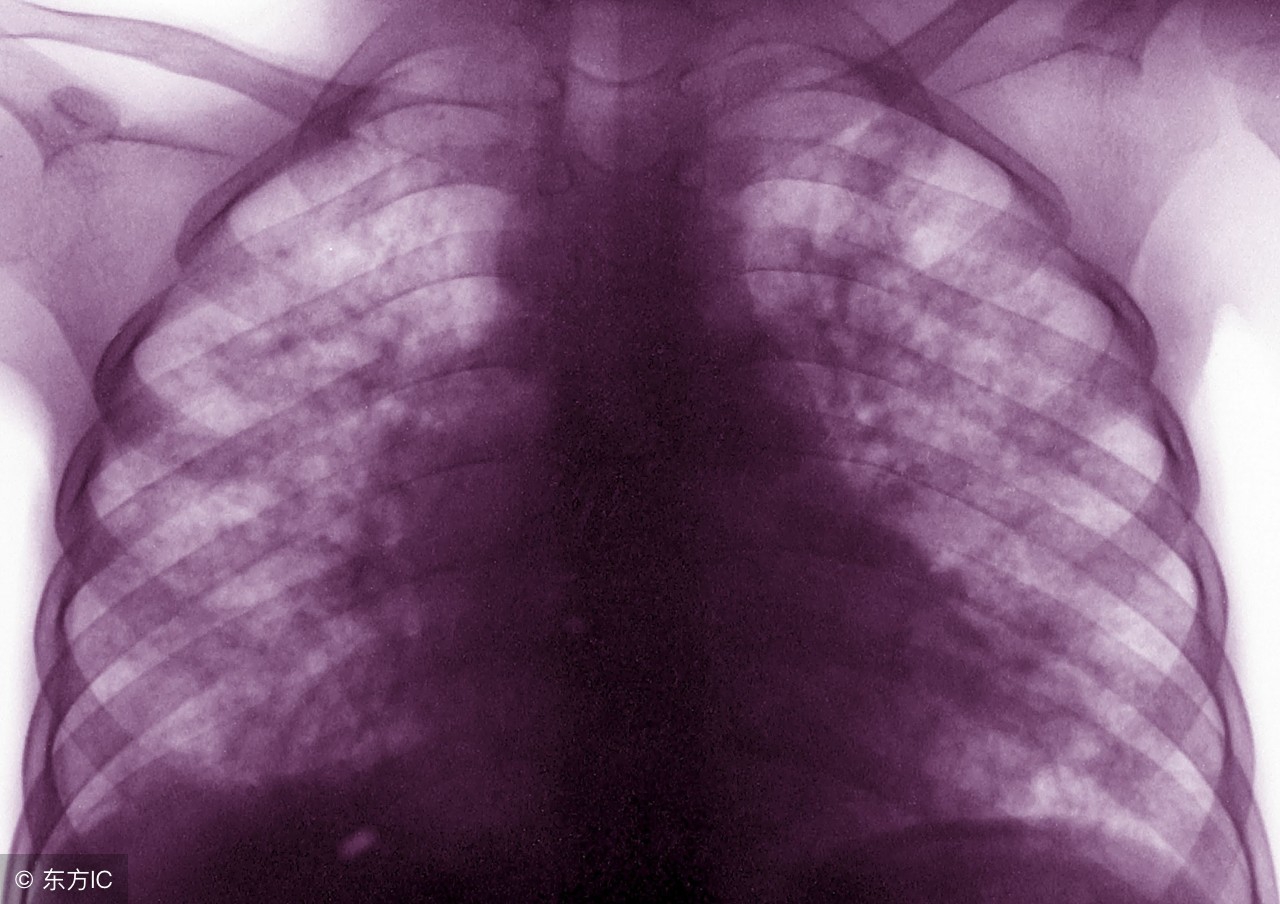

肺结核是结核病中最常见的一种,因为对肺结核认识不够很多人对该病都非常恐惧,因为肺结核具有高度的传染性,病程长等特点。一旦患病,患者本人及其家属总会惊慌失措不知如何是好。那么肺结核有哪些症状表现呢?

一、呼吸道症状:咳嗽、咳痰:血行播散型或轻型肺结核病人表现为干咳或少量的白色粘痰,干酪空洞或损坏型肺结核咳嗽剧烈,痰量增加,合并感染时为咳大量脓性痰。

咯血:相当多见,当肺部的任何病变损伤了血管时,便可出现咯血,咯血量的多少因血管损伤部位、大小不同而不同,痰中带血可因炎性病灶的毛细血管损伤所致,整口血痰是由于小的动静脉损伤,大咯血是损伤了大血管特别是肺动脉所致。对咯血病人,除应用止血剂外还应进行检查,如X线胸透或拍片,痰液检查,以明确咯血原因。